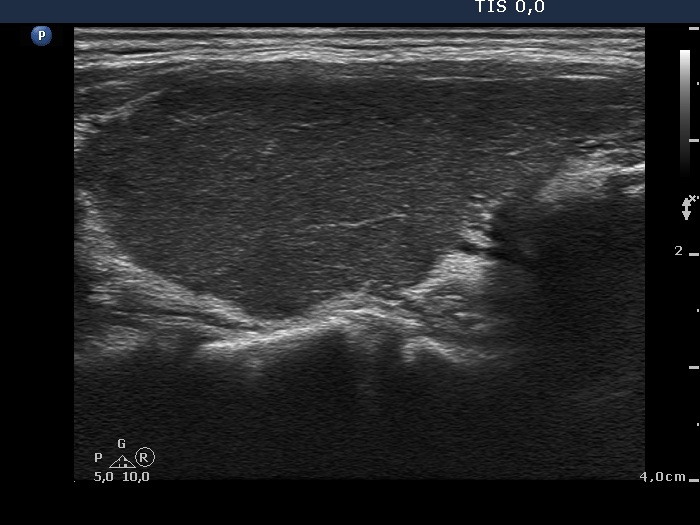

Consecutively operated patients with autoimmune thyroid disease - case 10 (1161) (ultrasonographic picture 5)

Left lobe, longitudinal view.